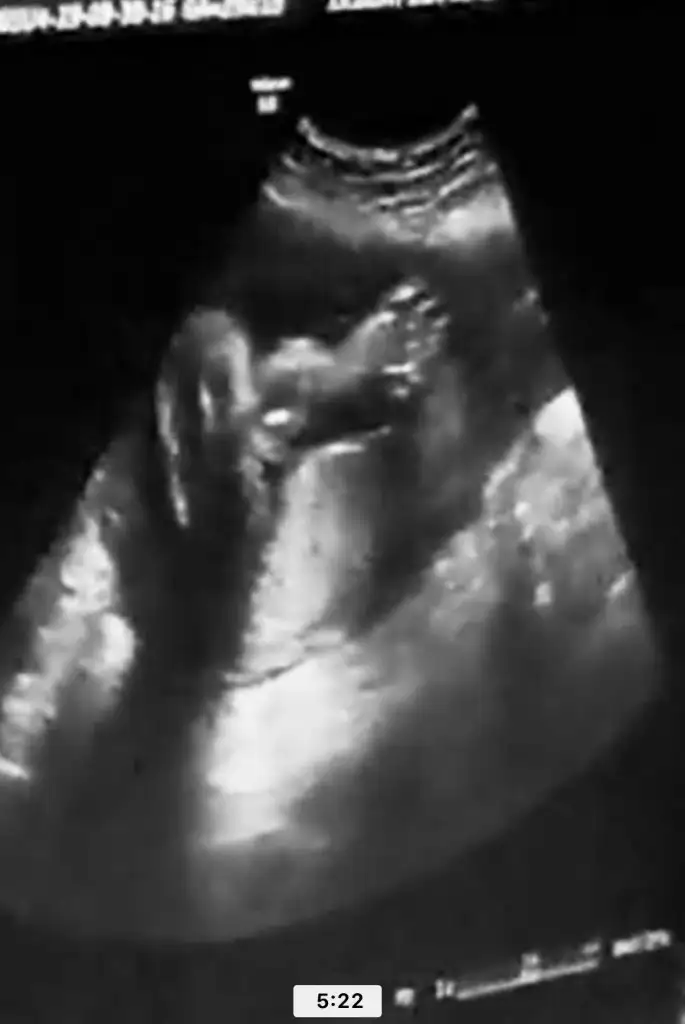

atarım bende buraya kuzum hemen merak etme :) bnde meraklıyımGerçekten çok güzel sürekli hareket halindeler ölçümü zorlaşıyor ama izlemesi çok zevkli rabbim hayırlısını versin sağlıklı olsun önemli olan bu ama insan duramıyor Ben bile merak ettim senin bebişini